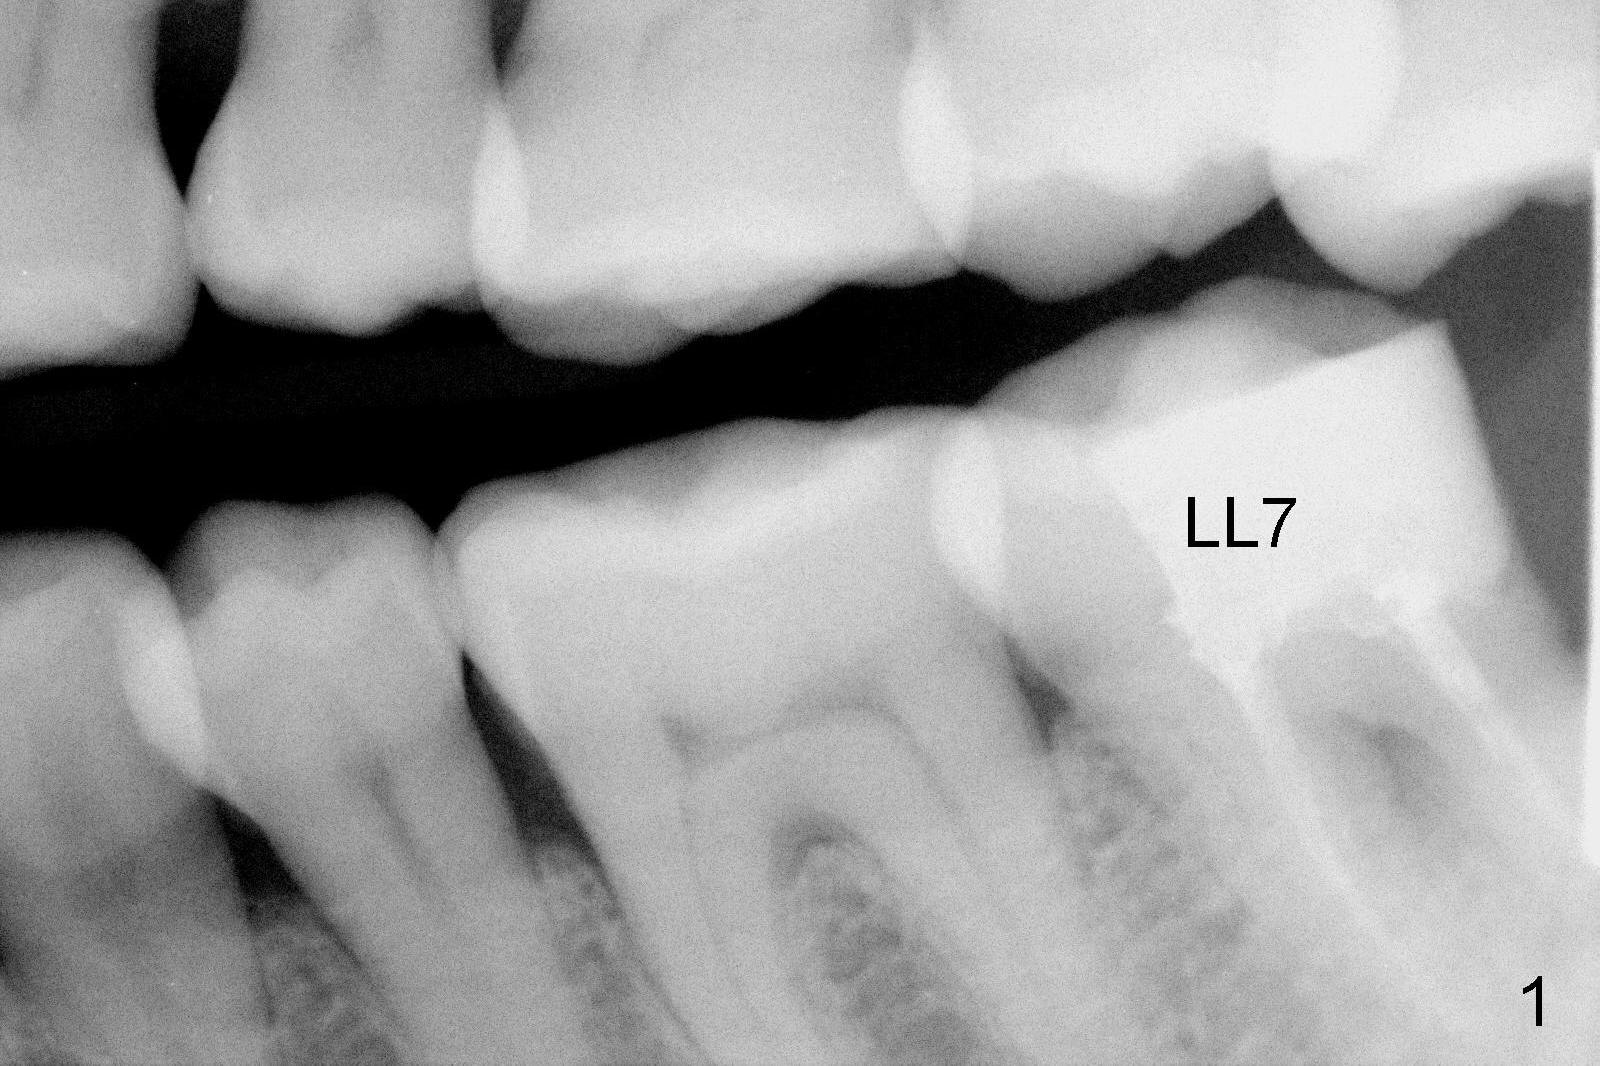

A 48-year-old lady is a dental phobic, requesting extraction of the lower left 2nd molar (Fig.1).   She returns for implant placement 9 months post extraction (Fig.2).  The ridge is mildly to moderately atrophic.  It appears that a 5x12 mm implant is appropriate for the site (Fig.3).  For safety, osteotomy is initiated at the depth of 10 mm; it appears that there is enough height for a 12 mm implant (Fig.4).  The depth is controlled by drill stopper (Fig.5 S).  Finally a 5x12 mm implant is apparently safely placed (Fig.6).  A healing abutment is placed and the incision is sutured with 4-0 Chromic gut (Fig.7).  Perio dressing is applied around the healing abutment for wound protection (Fig.8).  It appears that the healing abutment (Fig.8': *) helps stabilize the perio dressing, which remains in place 1 week postop.  When the perio dressing is removed, the wound around the healing abutment is healing (Fig.9).  There is no bone loss around the implant 3 months postop (Fig.10 (H: healing abutment), or 16 months postop (i.e., 9 months post cementation, Fig.11,12).  The patient complains of pain when she chews with the implant crown, but pain stops whenever she does not bite.  Percussion does not elicit any discomfort.  The gingiva is healthy.  There is possibility of the buccal plate being thin or the lingual plate being perforated in the submandibular fossa.  If the discomfort remains the same next 6 months, CBCT will be prescribed.